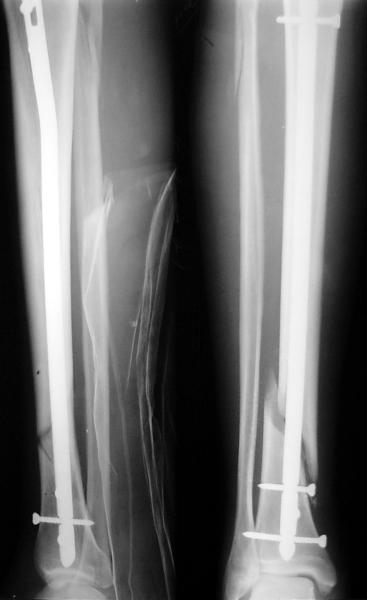

Как мне показать пример? Фото стоящего на одной оперированной конечности пациента? O! Пример, подвигнувший нас на некоторое изменение технологий. Пациент этот ходил с полной нагрузкой вопреки рекомендациям. В качестве подтверждения - сломанный проксимальный статический винт к 1 мес., а к 2 мес. - все остальные. Сейчас мы перешли на более fool-proof остесинтез.

Ok. А также и следующий, в 3 месяца.

Это наглядная демонстрация возможности ранней полной нагрузки при нестабильном по оси повреждении, причем не в самых благоприятных механических условиях - при плохом сопоставлении, со слабым фиксатором.

Сверху - один статический винт, а снизу - три. Что раньше сломается? Конечно, он потом и нижние сломал, и Вы правы, если бы верхний динамичесий винт уже уперся бы в нижний край отверстия, будь гвоздь подлинее, перфорировал бы сустав как пить дать.